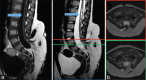

Surgical management of lipomyelomeningocele in children: Challenges and considerations

Figures